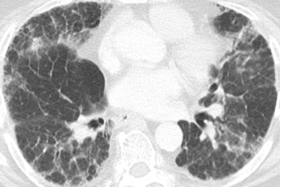

1、所谓急性HP,就是患者接触了较高水平的暴露,例如有患者喜欢饲养鸟类,尤其喜欢宠物鸽子,于是到交易市场去看,在这个过程中,可能出现了间断高水平暴露,于是一些易感个体就在很短的时间内(4到12小时)出现了流感样症状和呼吸道症状,而肺内则出现了一些磨玻璃影。

2、也有一些患者急性发作伴发热,劳力性呼吸困难、乏力和咳嗽,影像表现为小叶中央性的弥漫性的腺泡结节,称之为亚急性HP

3、还有些患者持续性低水平暴露,起病很隐匿,当我们发现时,已经出现了劳力性呼吸困难,干咳,体重减轻和乏力,而影像出现了既有磨玻璃影,也有肺纤维化的表现,称之为慢性HP

图:(从左至右)急性、亚急性、慢性